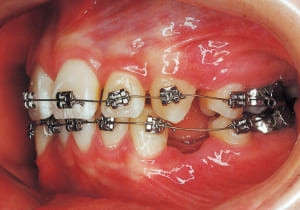

18 Treatment progress 4-11-’94

21

In the maxilla, insufficient space for canine eruption was inevitable, necessitating extraction as part of the treatment plan. The maxillary first premolars on both sides were extracted during routine observation to create space for canine eruption (14). Eventually, the canines erupted and settled into relatively favorable positions (15,19,20). In the mandibular dentition, crowding was also present, leading to extraction of the mandibular first premolars on both sides. Treatment with full bracket was then initiated (17).